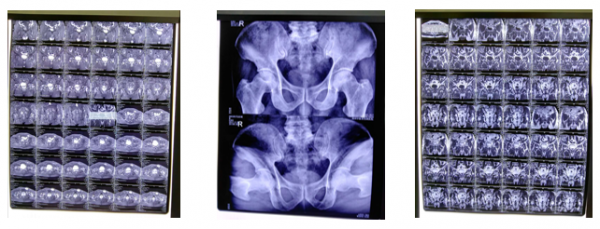

03:典型病例見證